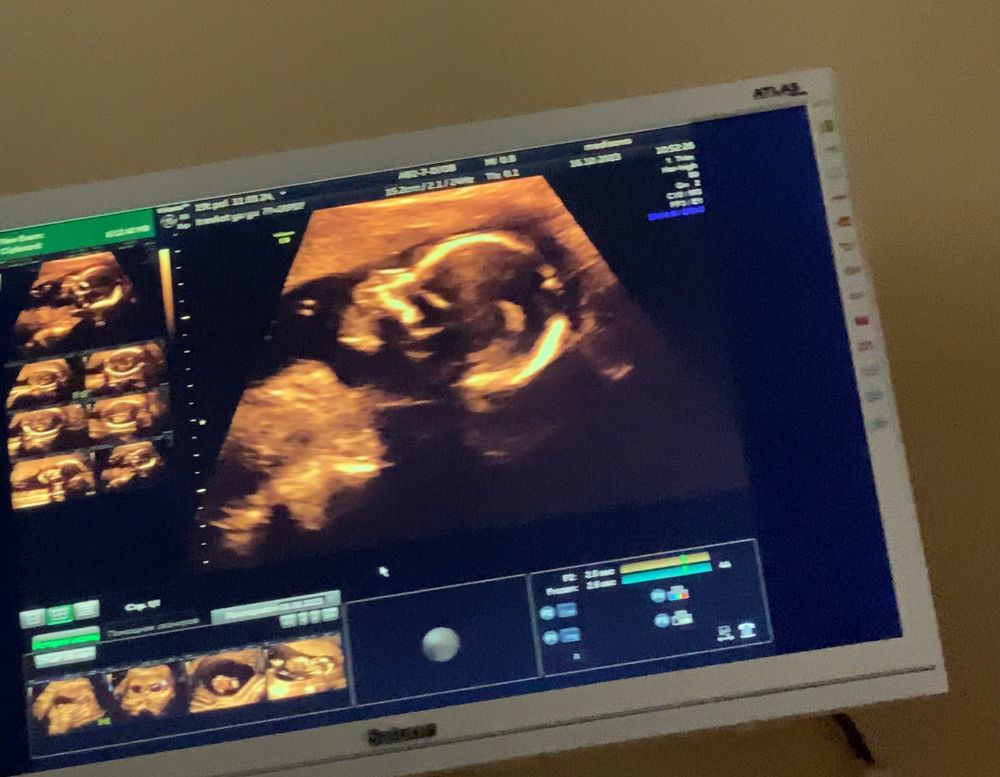

7.03 Путем КС появился на свет наш красавчик ❤️

21 неделя, мой вес 77.5,( вес ребенка почти 300 грам был на 19 недель) шевеления с 19 недели, мальчик )проблеми с дыханием у меня ,тяжело и мало кислорода, лежала в